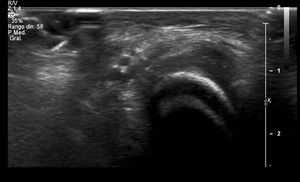

La ecografía (fig. 2) muestra un engrosamiento hipoecogénico del tejido celular subcutáneo, anterior a la articulación de Chopart, sin incremento de señal Doppler.

Los hallazgos clínicos y ecográficos son compatibles con callosidad talar, una entidad benigna poco frecuente en países occidentales1,2. Se caracteriza por la aparición de placas hiperqueratósicas indoloras en el dorso de los pies.